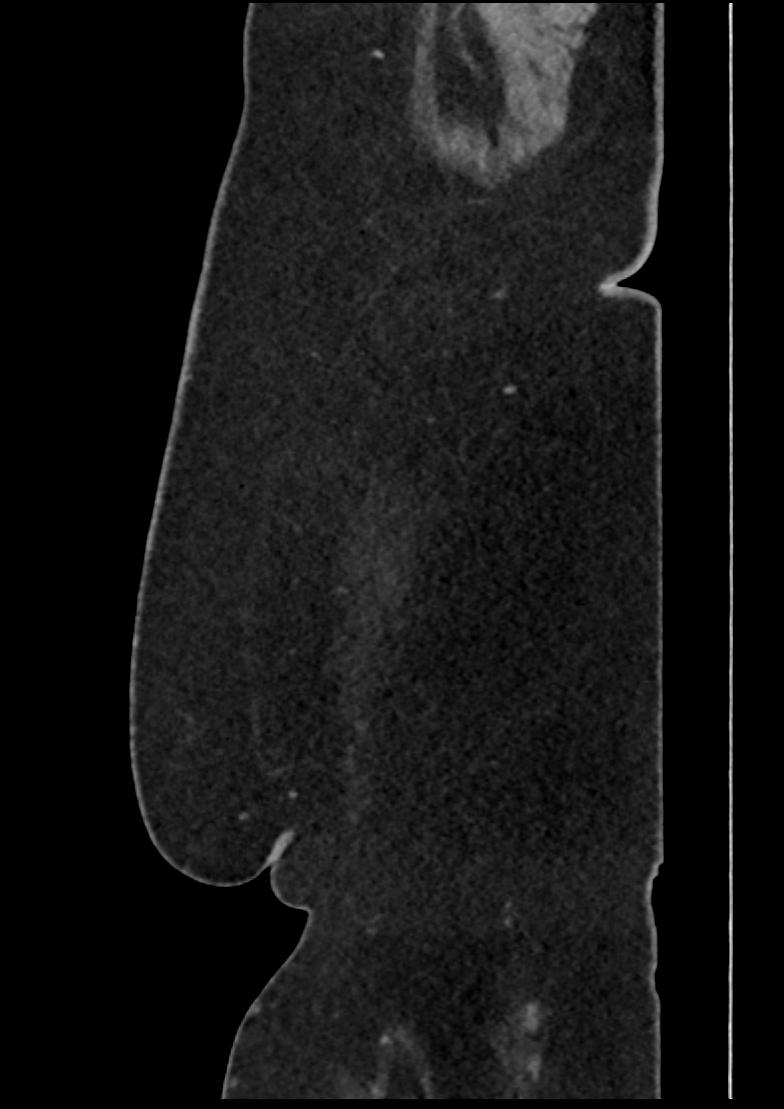

Patient: Padmakumar A. , *1988-04-24, PID: 3000069741773230809

Study Description: CT ABDOMEN

Image Series: Abdomen Sag 3mm [4]

<< Previous | Image 20 of 158 | Next >>